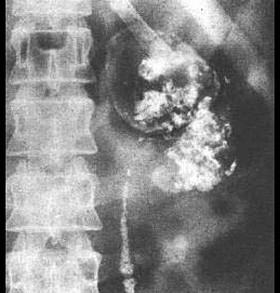

问题 关于泌尿系结核的病理,下列哪一项是错误的 ( )

选项 A、膀胱肌层纤维化和瘢痕收缩,造成膀胱挛缩 B、“肾自截”是泌尿系结核自行愈合的表现 C、结核性溃疡 D、纤维化病变,可使输尿管狭窄 E、结核结节形成

答案 B